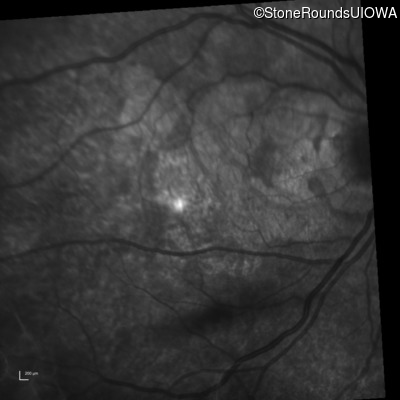

Infrared Fundus Photograph - Left - 20/200

Exemplar